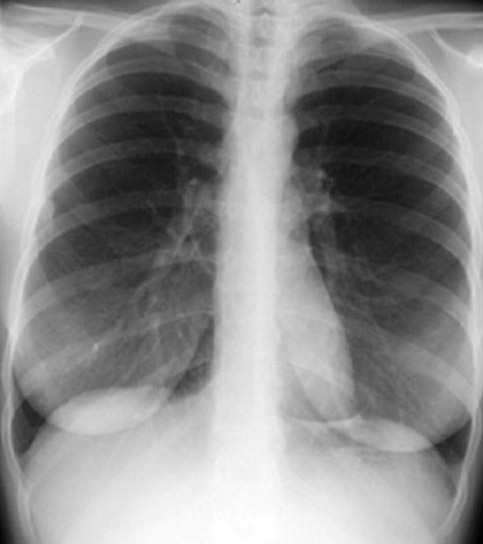

Inhomogenuity of Densities

The following densities are homogenous and symmetrical:

• Heart

• Pulmonary arteries

• Clavicles

• Breast

Naturally, the cardiac shadow is more dense over the spine and descending aorta. Densities of the left and right pulmonary artery should be the same. If you see inhomogenuity, it suggests that there is an additional density at that site either in front , behind, or at that level. Similarly asymmetry in clavicular densities should suggest retroclavicular lung lesion.